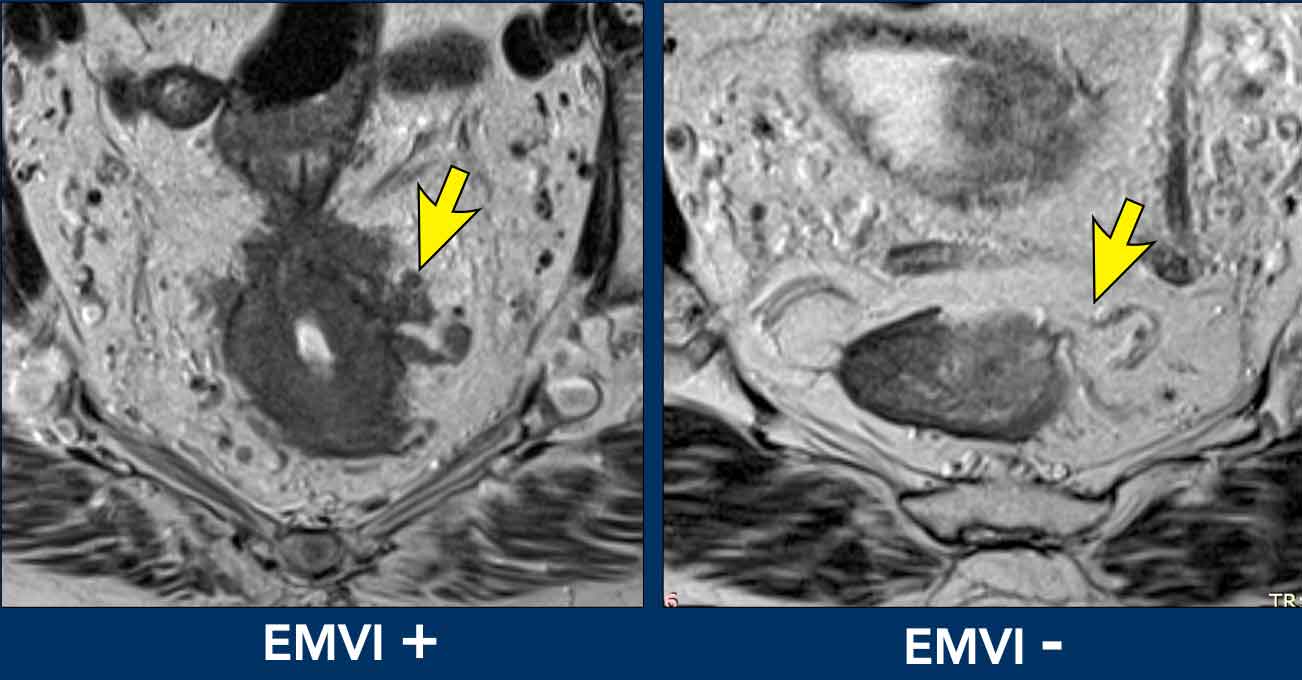

EMVI can be graded as follows [ref]:

• 0 = no nodular extension beyond the muscularis propria and no vessels adjacent to areas of tumor extension

• 1 = Minimal nodular extension or stranding, not in the vicinity of vascular structures

• 2 = stranding in the vicinity of extramural vessels, with vessel of normal caliber and no tumor signal extending into the vessels

• 3 = tumor signal extending into vessels, with normal or slightly expanded vessel contour

• 4 = tumor signal extending into vessels with clear disruption of vessel contour and/or nodular expansion of the vessels

Grades 3 and 4 should be reported as EMVI+ disease.

Grades 0-2 as EMVI-.

Image comparison

• Left (EMVI+): Tumor signal clearly extends into adjacent vessels, disrupting their contours.

• Right (EMVI-): Vessels maintain smooth contours with no tumor signal present.